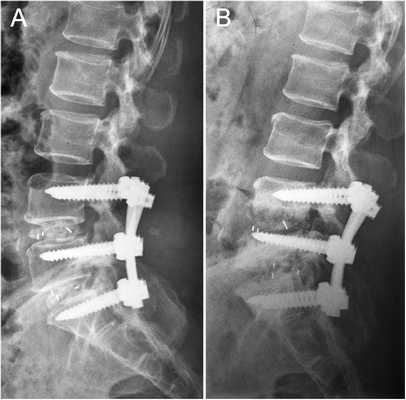

В 1-й группе пациентов выполняли вентральный внебрюшинный доступ к уровню LV—SI, тотальную дискэктомию с передней декомпрессией дурального мешка, во 2-й группе — декомпрессию дурального мешка и корешков дорзальным срединным доступом с установкой межтелового кейджа и транспедикулярной винтовой фиксацией для формирования спондилодеза.

Клинический пример. Пациентка К., 39 лет, обратилась с рецидивом болевого синдрома после выполненной 6 мес назад микрохирургической интерляминэктомии на уровне LV—SI, удаления грыжи диска. По данным магнитно-резонансной томографии выявлены рецидив грыжи диска без миграции фрагмента в краниальном и каудальном направлениях, снижение высоты диска на 75% от исходной, что в совокупности с остеофитами вызывало компрессию корешка LV справа. С учетом необходимости восстановить высоту диска с заданным углом принято решение о целесообразности тотальной дискэктомии из забрюшинного доступа с межтеловым эндопротезированием. Угол операционного действия составил 15°. Несмотря на столь небольшой угол операционного действия, рана длинной 83 мм и глубиной 94 мм при угле наклона оси операционного действия в 78° позволили без затруднений технически выполнить декомпрессию дурального мешка и нервных корешков. Длительность операции составила 92 мин, кровопотеря — 20 мл.

Клинический пример. Пациентка Т., 42 года, обратилась с признаками рецидива грыжи диска LV—SI, подтвержденной данными магнитно-резонансной томографий. В анамнезе перенесенный перитонит, и как следствие — спаечный процесс в брюшной полости и по левому флангу забрюшинно в местах, в которых стояли дренажи. В связи с этим пациентке выполнена операция из дорзального доступа: декомпрессия дурального мешка, корешков LV, SI справа, удаление рецидивной грыжи с межтеловым корпородезом кейджем и транспедикулярной фиксацией LV—SI. Угол операционного действия составил 84°, длина раны — 98 мм, глубина раны — 74 мм, угол наклона оси операционного действия составил 82°. При этом, несмотря на удовлетворительный обзор и комфортные условия для выполнения операции, доступ осуществлялся с техническими трудностями через рубцово-измененные ткани, что потребовало длительного и деликатного выделения нервных корешков на фоне кровотечения из эпидуральных вен, в связи с чем время операции составило 167 мин, кровопотеря — 430 мл.